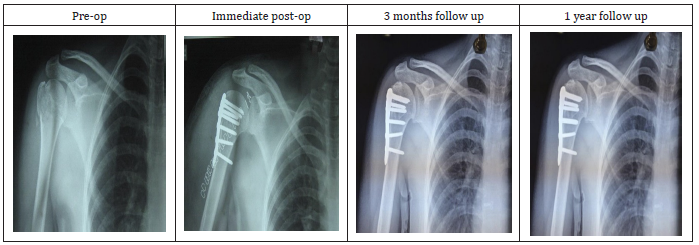

Figure 1:Radiographs of fracture of surgical neck of humerus with PHN.

Figure 3:Radiographs of fracture of surgical neck of humerus with PHILOS.